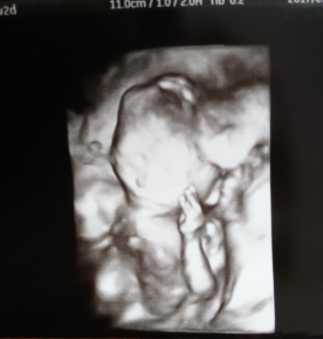

18週1日(18w1d・男の子)|なお410 さん(22歳)

エコー写真撮影時のエピソード:

初めて性別が分かった日のエコーです。両手をばんざいしている姿が愛しくとっても可愛いです!私はどこを見て男の子だったのか分からなかったですが、元気な男の子、予想通りでした!家族みんなで楽しみにまってます!すくすく育ってほしいです!待ち遠しい!